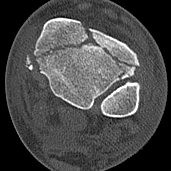

CT scan

Commonly 3 fracture configurations

- medial malleolus

- posterolateral fragment / Volkmann

- anterolateral fragment / Chaput